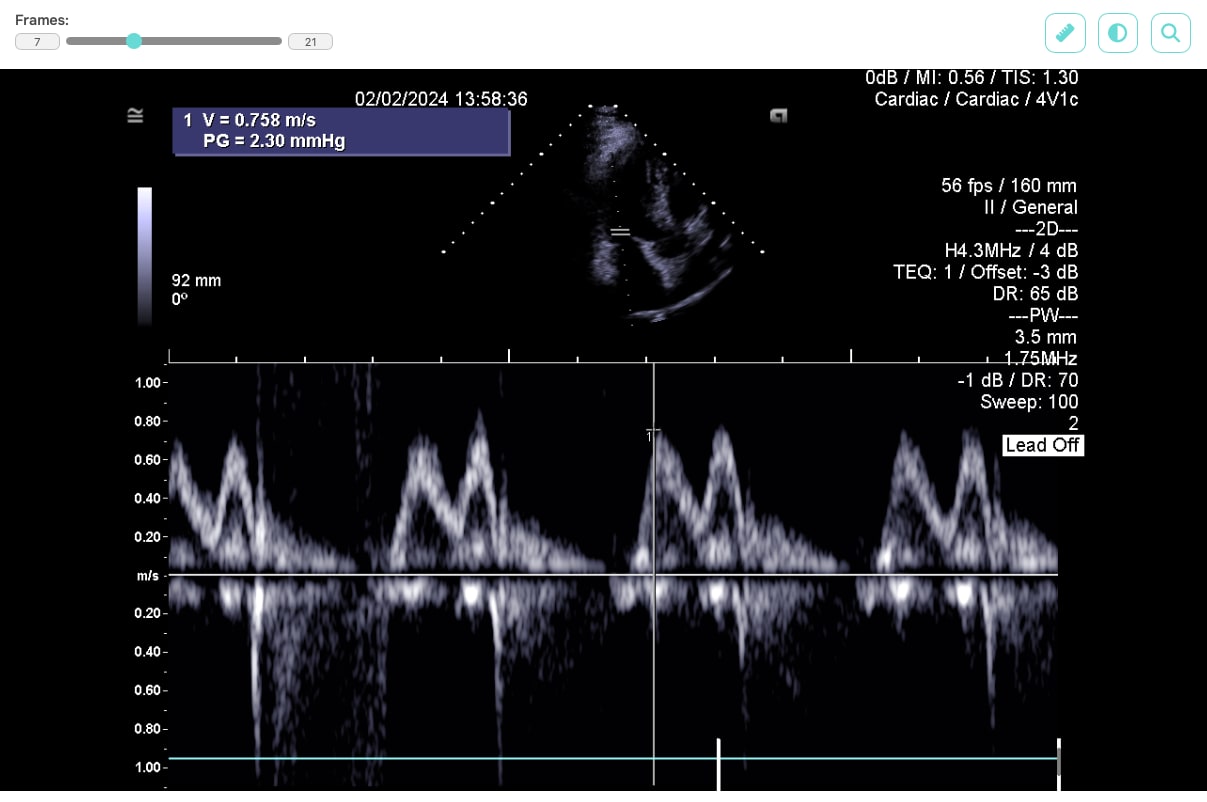

For displaying data on the web, we selected the JavaScript library Cornerstone3D, which not only allows DICOM files to be viewed but also provides features such as adjusting brightness and contrast, or using a ruler to measure distances between displayed parts of the patient’s body.

By including a DICOM format viewer into our custom web application, we can precisely manage data access without compromising the quality of the user interface, ensuring that each clinician only sees the examinations of their own patients. Connection to the application will be secured using HTTPS technology and standard web server security measures on which the application will run.